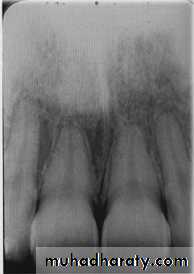

Invasive irregular border-bone destruction/SCC

Blending border. A gradual transition from the dense trabecular of sclerosing osteitis (short arrow) to the normal trabecular pattern (long arrow).